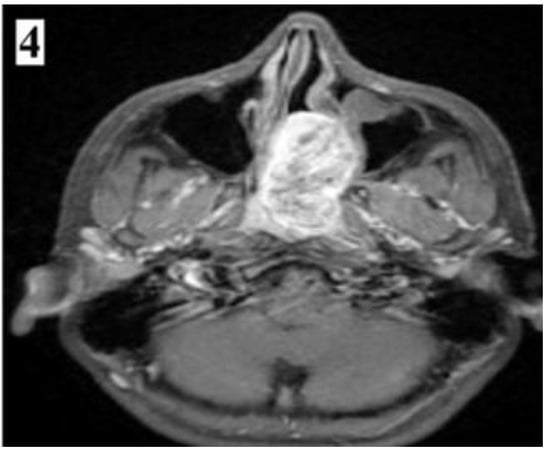

IA—Limited to posterior nares and/or nasopharyngeal vault; IB—IA + involvement of at least one paranasal sinus (part 1).

Figure 4.

IA—Limited to posterior nares and/or nasopharyngeal vault; IB—IA + involvement of at least one paranasal sinus (part 2).

Magnetic resonance imaging provides important details about the extension of the tumour. T2 weighted sequences are indicated to differentiate tumour tissue from mucus, while T1 weighted sequences are indicated for better assessment of intracranial extension [5].